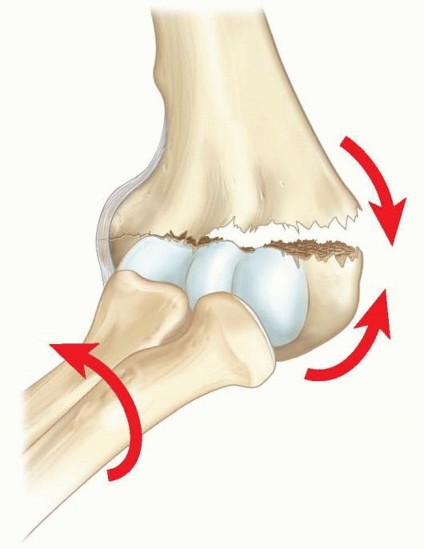

Chapter 28 Distal Femoral Physeal Fractures Martin J. Herman DEFINITION Fractures of the distal femoral physi…